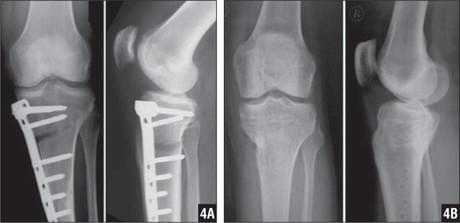

Спицами Киршнера в основном фиксируют мелкие кости и суставы (пальцы стопы и кисти, плюсневые и пястные кости). Иммобилизация проводится, как правило, в течение 4-6 недель после операции. Факсация может быть как наружной, т.е. конец спицы находится над поверхностью кожи, так и внутренней, т.е. спица полностью погружена под кожу для снижения риска инфицирования и неудобств пациента. Исполюзуется для временной фиксации. Так же существует погружной остеосинтез спицами и проволокой для остеосинтеза более крупных костей по Веберу, например, при:

Удаление спиц и проволоки после остеосинтеза надколенника по Веберу

При переломах надколенника (коленной чашечки) со смещением отломков выполняется операция остеосинтеза, т.е. скрепление костных фрагментов для восстановления целостности кости и соответственно функции коленного сустава. Так как при отказе от операции пациент рискует остаться инвалидом.

Для остеосинтеза надколенника в подавляющем большинстве случаев используется методика Вебера. Когда костные отломки скрепляются двумя титановыми спицами Киршнера и дополнительно стягиваются титановой проволокой 8 образно. Это позволяет быстро и очень эффективно восстановить поврежденную кость и что немаловажно металлоконструкция минимальна по стоимости. Но у нее есть один большой минус. Очень часто пациенты испытывают дискомфорт и боль в области мпиц и проволоки, так как она находится правктичекски сразу под кожей. Поэтому часто выполняется удаление металлоконструкции из надколенника.

После того как кость срослась и металлоконструкция выполнила свою функцию ее можно удалить. Полное сращение кости происходит за 6- 8 месяцев, в некоторых случая 1 год. Именно спустя этот срок можно удалять металл.

Операция зачастую выполняется в условиях дневного стационара, т.е. через несколько часов после операции пациент может уйти домой. Анестезия местная, проводниковая либо наркоз. Непосредственно сама операция по времени занимает 30 минут. Найти проволку и спицы, как правило, не представляет труда для хирурга. После того как металлоконструкция удалена проводится зашивание раны и наложение асептической повязки. Пациент приходит на перевязки в первые сутки, далее можно перевязываться самостоятельно либо в лечебном учреждении рядом с домом. Швы необходимо снять через 14 дней после операции. В раннем послеоперационном периоде назначаются обезболивающие и антибактериальные препараты.

Примерно через 1 месяц после операции по удалению металлоконструкции из надколенника можно постепенно увеличивать нагрузку и возвращаться в свой обычный ритм жизни.